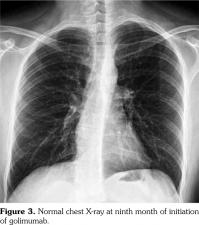

Lymph node biopsy was performed by broncoscopy and endobronchial ultrasonography. Biopsy result was compatible with granulomatous disease. All the infectious studies performed on pulmonary lymph node tissues were negative. Angiotensin converting enzyme level was at the upper limit with a value of 47.6 U/L (normal: 8-52 U/L). Sarcoidosis was found to be compatible with the condition after excluding tuberculosis. Etanercept was ceased following the diagnosis of sarcoidosis. No additional medical treatment was suggested for sarcoidosis. Non- steroid anti-inflammatory drugs were prescribed for the control of AS. Five months later, follow- up thorax computed tomography scan showed resolution of the mediastinal lymphadenopathies (Figure 2).